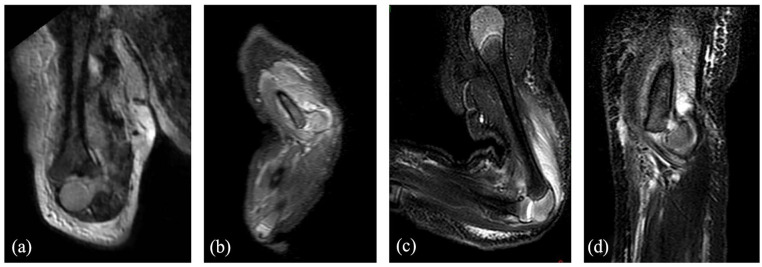

Methods: All consecutive infants treated between 2005 and 2020 for a transphyseal fracture of the distal humerus before the age of 6 months were retrospectively included. All radiological examinations were analyzed (X-ray, ultrasound, and magnetic resonance imaging (MRI)) as well as the therapeutic management (orthopedic or surgical treatment). The patients were seen at outpatient clinic visits with a minimum of 2-year follow-up.

Results: Nine newborns were treated. The main cause was an obstetrical traumatism (n = 8). The diagnosis was made on physical examination and addressed by obstetric departments with standard biplanar radiographs in four cases. The fracture was suspected on physical examination in the remaining five cases and confirmed by complementary imaging (ultrasound (2), MRI (1), and both (3)). A total of six patients were treated conservatively and three surgically with an open reduction. At a mean follow-up of 79 months, two complications occurred: one axillary abscess due to the cast and one cubitus varus deformity. All children had a full functional recovery.